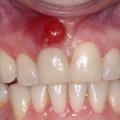

Фото 4. Гранулёма, возникшая из-за периодонтита. Представляет из себя припухлость на десне.